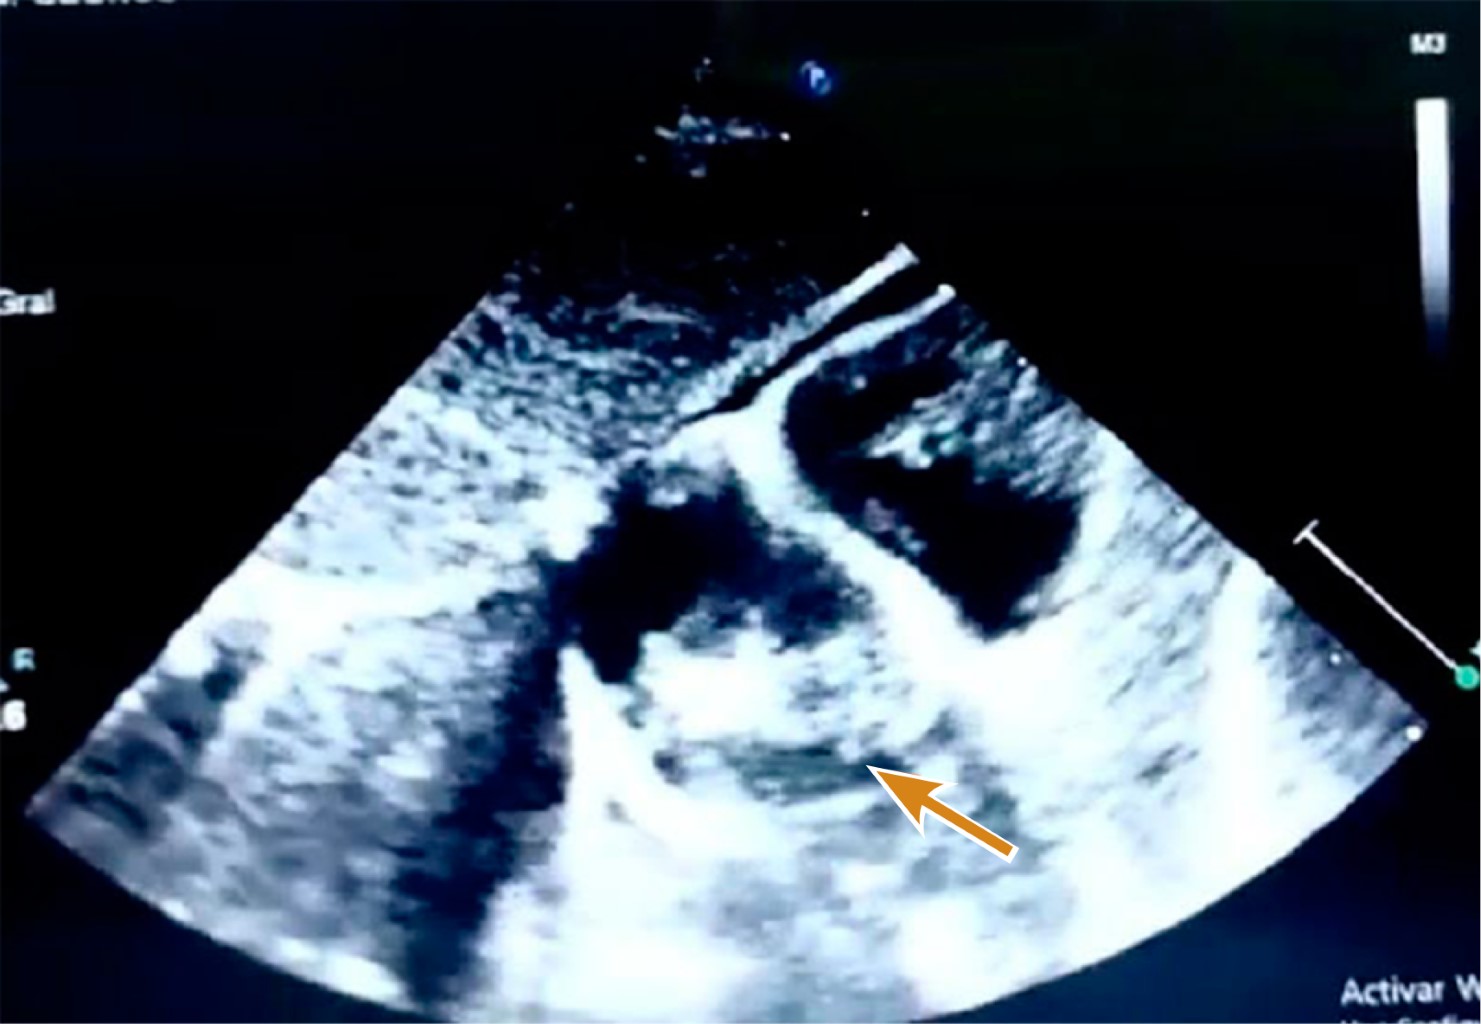

Intracardiac hemangioma in an infant

Introduction: intracardiac tumors in children are rare, but most are benign. In general, these tumors do not cause symptoms, but as they increase in size, they can lead to heart failure. Case presentation: three-month-old male patient who had an intrauterine diagnosis of mediastinal mass. At birth he was asymptomatic. Resection of right atrial tumor was performed. The pathology report indicated that it was an intracardiac hemangioma. The patient has had a favorable evolution. Conclusions: intracardiac tumors are a rare entity in pediatrics, which are generally detected accidentally.

Figure 4